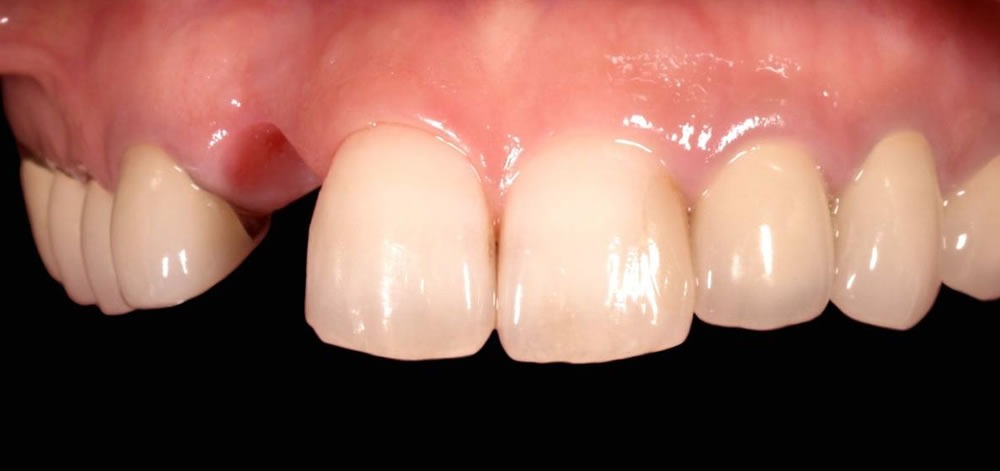

初診時

他医院で抜歯だけ行い、前歯のインプラントを希望して当院へ来院。